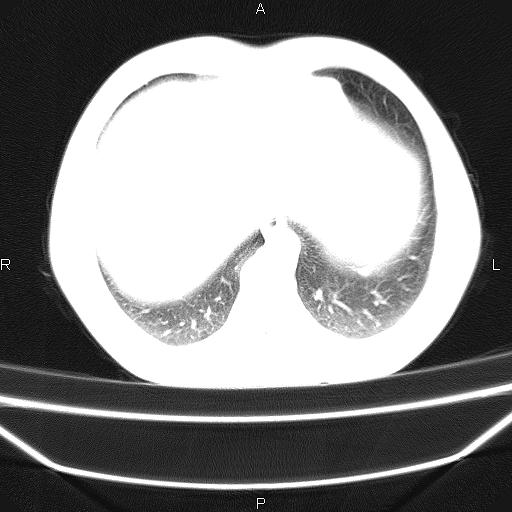

标题: CT26599:男,40岁。间断发热,咳嗽二十余日。体温最高达38.9 [打印本页]

标题: CT26599:男,40岁。间断发热,咳嗽二十余日。体温最高达38.9

患者,男,40岁。间断发热,咳嗽二十余日。体温最高达38.9° 在当地诊所抗炎治疗三天后体温降至正常,患者自行停药。今又发热。胸片示,左下肺阴影。

标题: 左下肺片状高密度影

左下肺片状高密度影,境界模糊,密度不均,考虑感染性病变可能性大,建议抗炎治疗后复查。左肺门增大,不除外占位性病变,必要时支气管镜检。